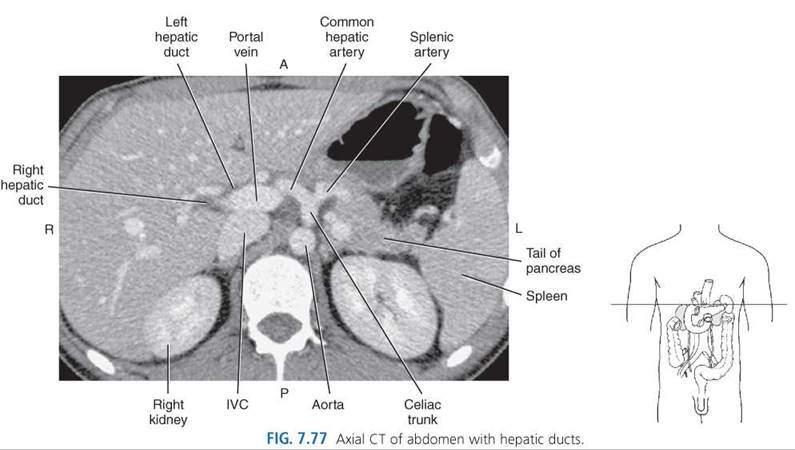

The widest portion, the body, gently tapers superiorly into the neck. The narrow neck lies to the right of the porta hepatis and continues as the cystic duct. The neck contains circular muscles that create spiral folds within the mucosa called the spiral valves of Heister (Fig. 7.70). These valves are particularly prominent at the bend formed by the neck and cystic duct, a common area for gallbladder impaction during acute or chronic cholecystitis. The gallbladder has a muscular wall that contracts when stimulated by the hormone cholecystokinin forcing bile through the extrahepatic biliary system into the duodenum. Cholecystokinin is secreted by cells in the duodenum as a response to ingestion of fat and protein into the stomach or duodenum. Bile is an alkaline fluid formed within the liver and stored in the gallbladder to be discharged into the duodenum for assistance in the digestion and absorption of fats and elimination of cholesterol and bilirubin from the body. It is collected for transport to the gallbladder by the intrahepatic bile ducts. The intrahepatic bile ducts run beside the hepatic arteries and portal veins throughout the liver parenchyma. The intrahepatic ducts merge into successively larger ducts as they follow a course from the periphery to the central portion of the liver, eventually forming the right and left hepatic ducts (Figs. 7.68-7.71). The right and left hepatic ducts unite at the porta hepatis to form the proximal portion of the common hepatic duct (CHD), which marks the beginning of the extrahepatic biliary system (Fig. 7.69).

The CHD is located anterior to the portal vein and lateral to the hepatic artery in its caudal descent from the porta hepatis. As the CHD descends in the free border of the lesser omentum, it is joined from the right by the cystic duct to form the common bile duct (CBD). The CBD continues a caudal descent along with the hepatic artery and portal vein within the hepatoduodenal ligament (Fig. 7.68). It curves slightly to the right, away from the portal vein, then courses posterior and medial to the first part of the duodenum behind the head of the pancreas (Figs. 7.71, 7.72, and 7.75-7.79). The CBD follows a groove on the posterior surface of the pancreatic head, then pierces the medial wall of the second part of the duodenum along with the main pancreatic duct (duct of Wirsung) through the ampulla of Vater (Fig. 7.69). The ends of both ducts are surrounded by the circular muscle fibers of the sphincter of Oddi (Fig. 7.70).